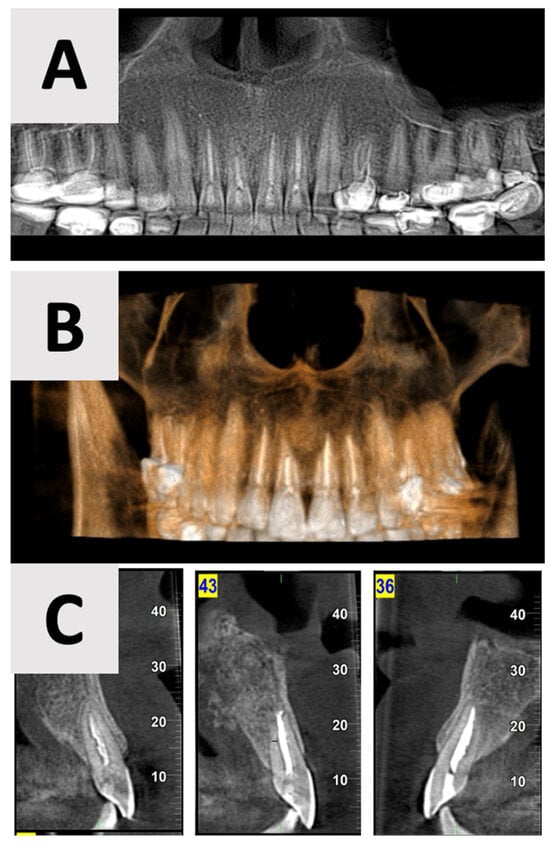

The surgical phase of cyst enucleation (Figure 3) was initiated following the six-month marsupialization period. Local anesthesia was administered using Cook-Waite® Lidocaine HCl 2% and Epinephrine 1:100,000 Injection (Septodont, Saint-Maur-des-Fossés, France). The surgical approach began with intrasulcular incisions extending from the right to left maxillary canines. These were complemented by vertical releasing incisions at the transitional line angles of both maxillary canines, facilitating optimal flap design and access (Figure 3C). A full thickness mucoperiosteal flap was elevated, exposing the bony architecture and revealing the entry point of the previously placed rubber drain (Figure 3D).

Figure 3.

Clinical stages of cyst management and removal. (A) Intraoral view showing the rubber drain in situ just before the end of marsupialization. (B) Palatal view demonstrating resolution of palatal swelling. (C) Surgical flap design with intrasulcular incisions from right to left maxillary canines and vertical releasing incisions at the transitional line angles. (D) Intraoperative view after full thickness mucoperiosteal flap elevation, revealing the bony entry point of the rubber drain. (E) Clinical view of the completely enucleated cyst specimen.

Complete enucleation of the cystic tissue was performed using specialized sinus augmentation curettes (Kohler Medizintechnik GmbH, Stockach, Germany), ensuring thorough removal of all pathological tissue while preserving surrounding vital structures. Following enucleation, the surgical site was thoroughly irrigated with sterile saline to remove any debris and assess for any remaining cystic tissue. The excised specimen (Figure 3E) was immediately fixed in 10% neutral buffered formalin and sent for histopathological examination to confirm the diagnosis.